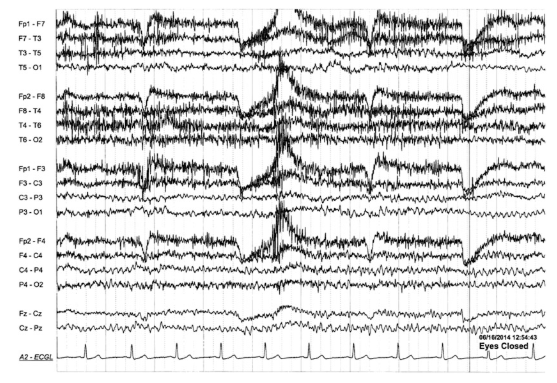

1

Q

A

Electrode pop